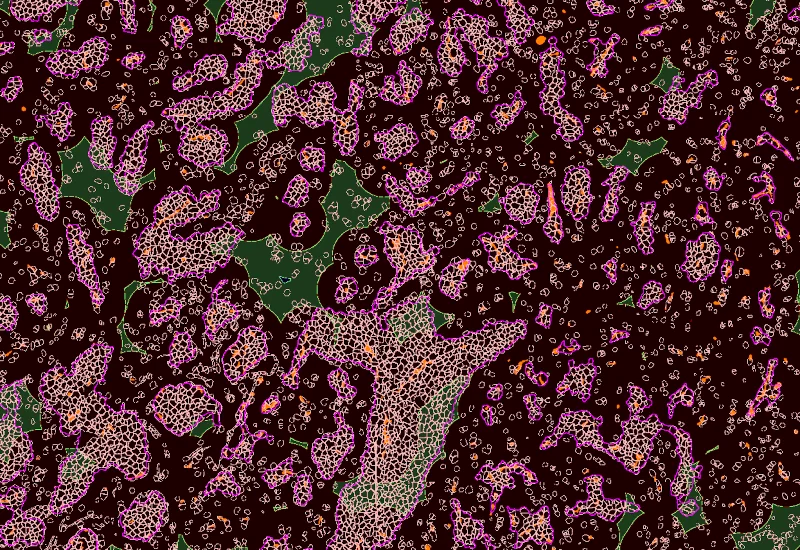

Tumor/Stroma/lymphoid cluster detection